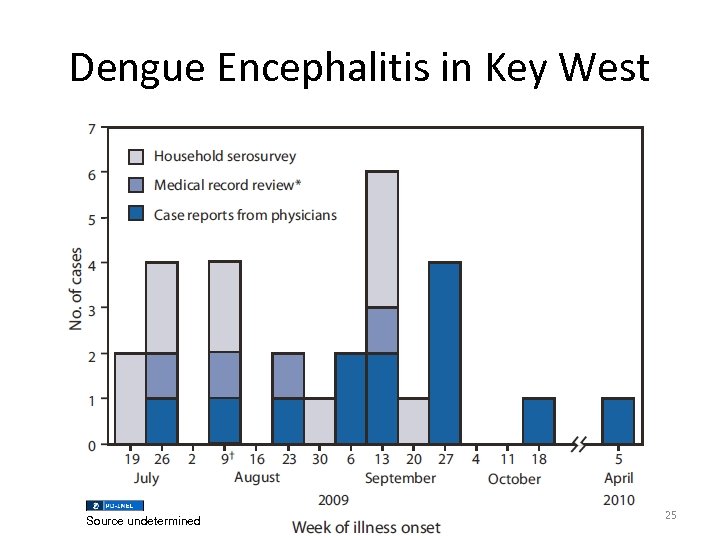

Dengue Encephalitis in Key West Source undetermined 25